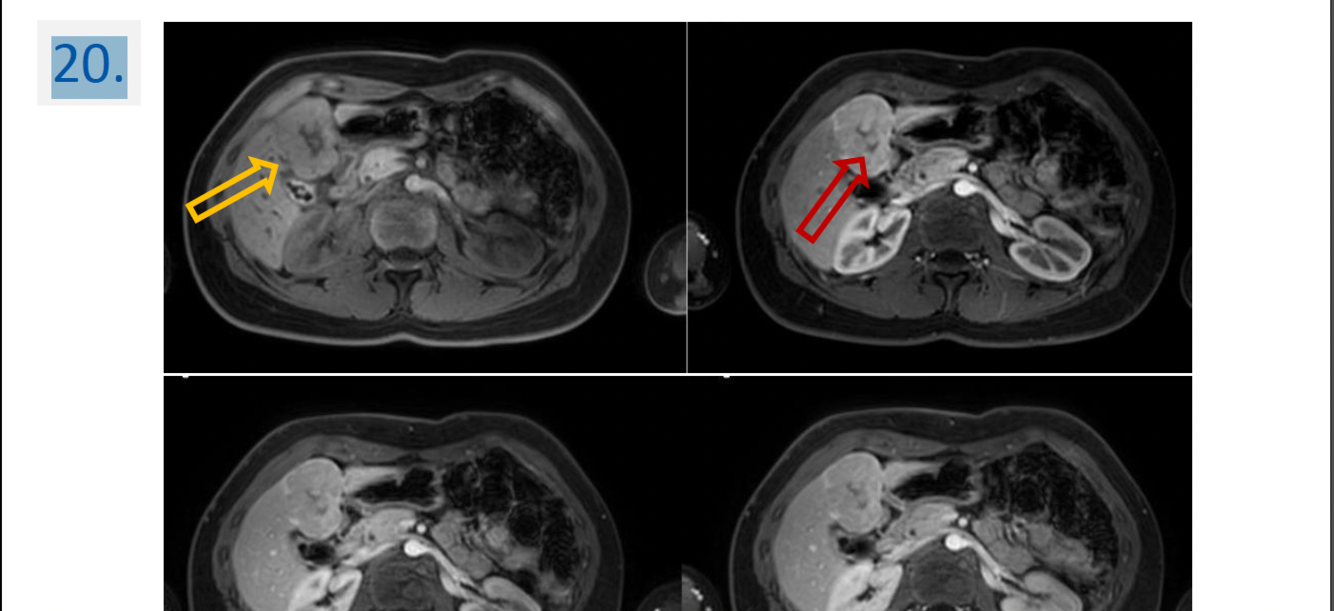

20

Modality:“mDIXON” dynamic contrast-enhanced MR after iv. gadolinium

(noncontrast, arterial phase, portal phase, venous phase)

Region:

upper abdominal MR study (axial view)

Diagnosis:

hepatic focal nodular hyperplasia (FNH)